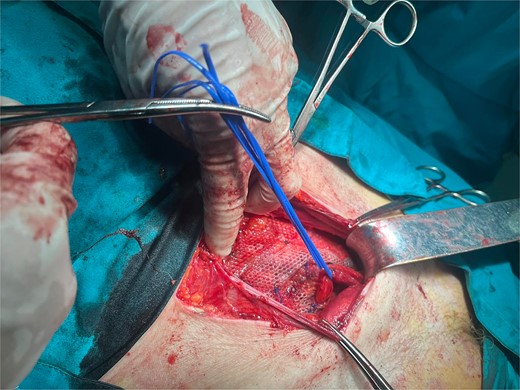

A 72-year-old patient, in good physical condition with a BMI of 26.1, came for an examination due to swelling in the right lateral abdominal wall without swelling of the scrotum. The patient was operated on for a right-sided inguinal hernia as an 8-year-old boy, but there was no appropriate medical documentation for the operative technique used. A month ago, besides the swelling, he experienced occasional abdominal pain and difficulties during physical activities in his garden. During clinical examination, a soft swelling in the right lateral abdominal wall, compressible under palpation was ascertained (Fig. 1). The abdominal ultrasound and contrast abdominal CT showed a thinned right abdominal wall with superficial intestinal loops and the differential diagnosis of a large recurrent inguinal or Spigelian hernia was presumed (Fig. 2). The patient received one dose of prophylactic cephalosporin preoperatively, and was operated on under general endotracheal anesthesia, in a supine position with a lumbar pillow placed for a slight tilt to the left. A right lateral lumbar-inguinal skin incision 4–5 cm above the anterior superior iliac spine in a horizontal direction following the lumbar dermatomal lines was performed. Subcutaneous fat was gently separated and the hernial sac dissection went to its apex below the right costal arch and base to the deep inguinal opening. When the sac was completely freed, the final diagnosis of giant recurrent indirect inguinal hernia (Fig. 3), and the sac with its content was repositioned in the abdominal cavity without opening the abdominal cavity and partial closure of the internal iliac ring was performed with resorptive sutures. After the dissection of the inguinal ligament up to the pubic tubercle (without extending the skin incision) a 15 × 12 cm polypropylene mesh was placed (Fig. 4), fixed to the pubic tuberculum and conjoint tendon with a laparoscopic taker (Fig. 5), and the ileopubic ligament partly with individual and partly with continuous non-absorbable polypropylene 2/0 suture. An opening for the spermatic cord was provided and medially the mesh was fixed with individual resorptive stitches (Fig. 6). The aponeurosis of the external oblique muscle was closed as much as it allowed to be approximated followed by individual subcutaneous and skin stitches (Fig. 7). The operating time was 65 minutes without blood loss and the patient had a quick and satisfactory recovery. He was discharged from the hospital on the third post-op day, and the skin stitches were removed on the 14th day. One month after the surgical treatment the patient was in good condition without any complaints (Fig. 8).

Mesh fixation to the pubic tuberculum and conjoint tendon with a laparoscopic taker